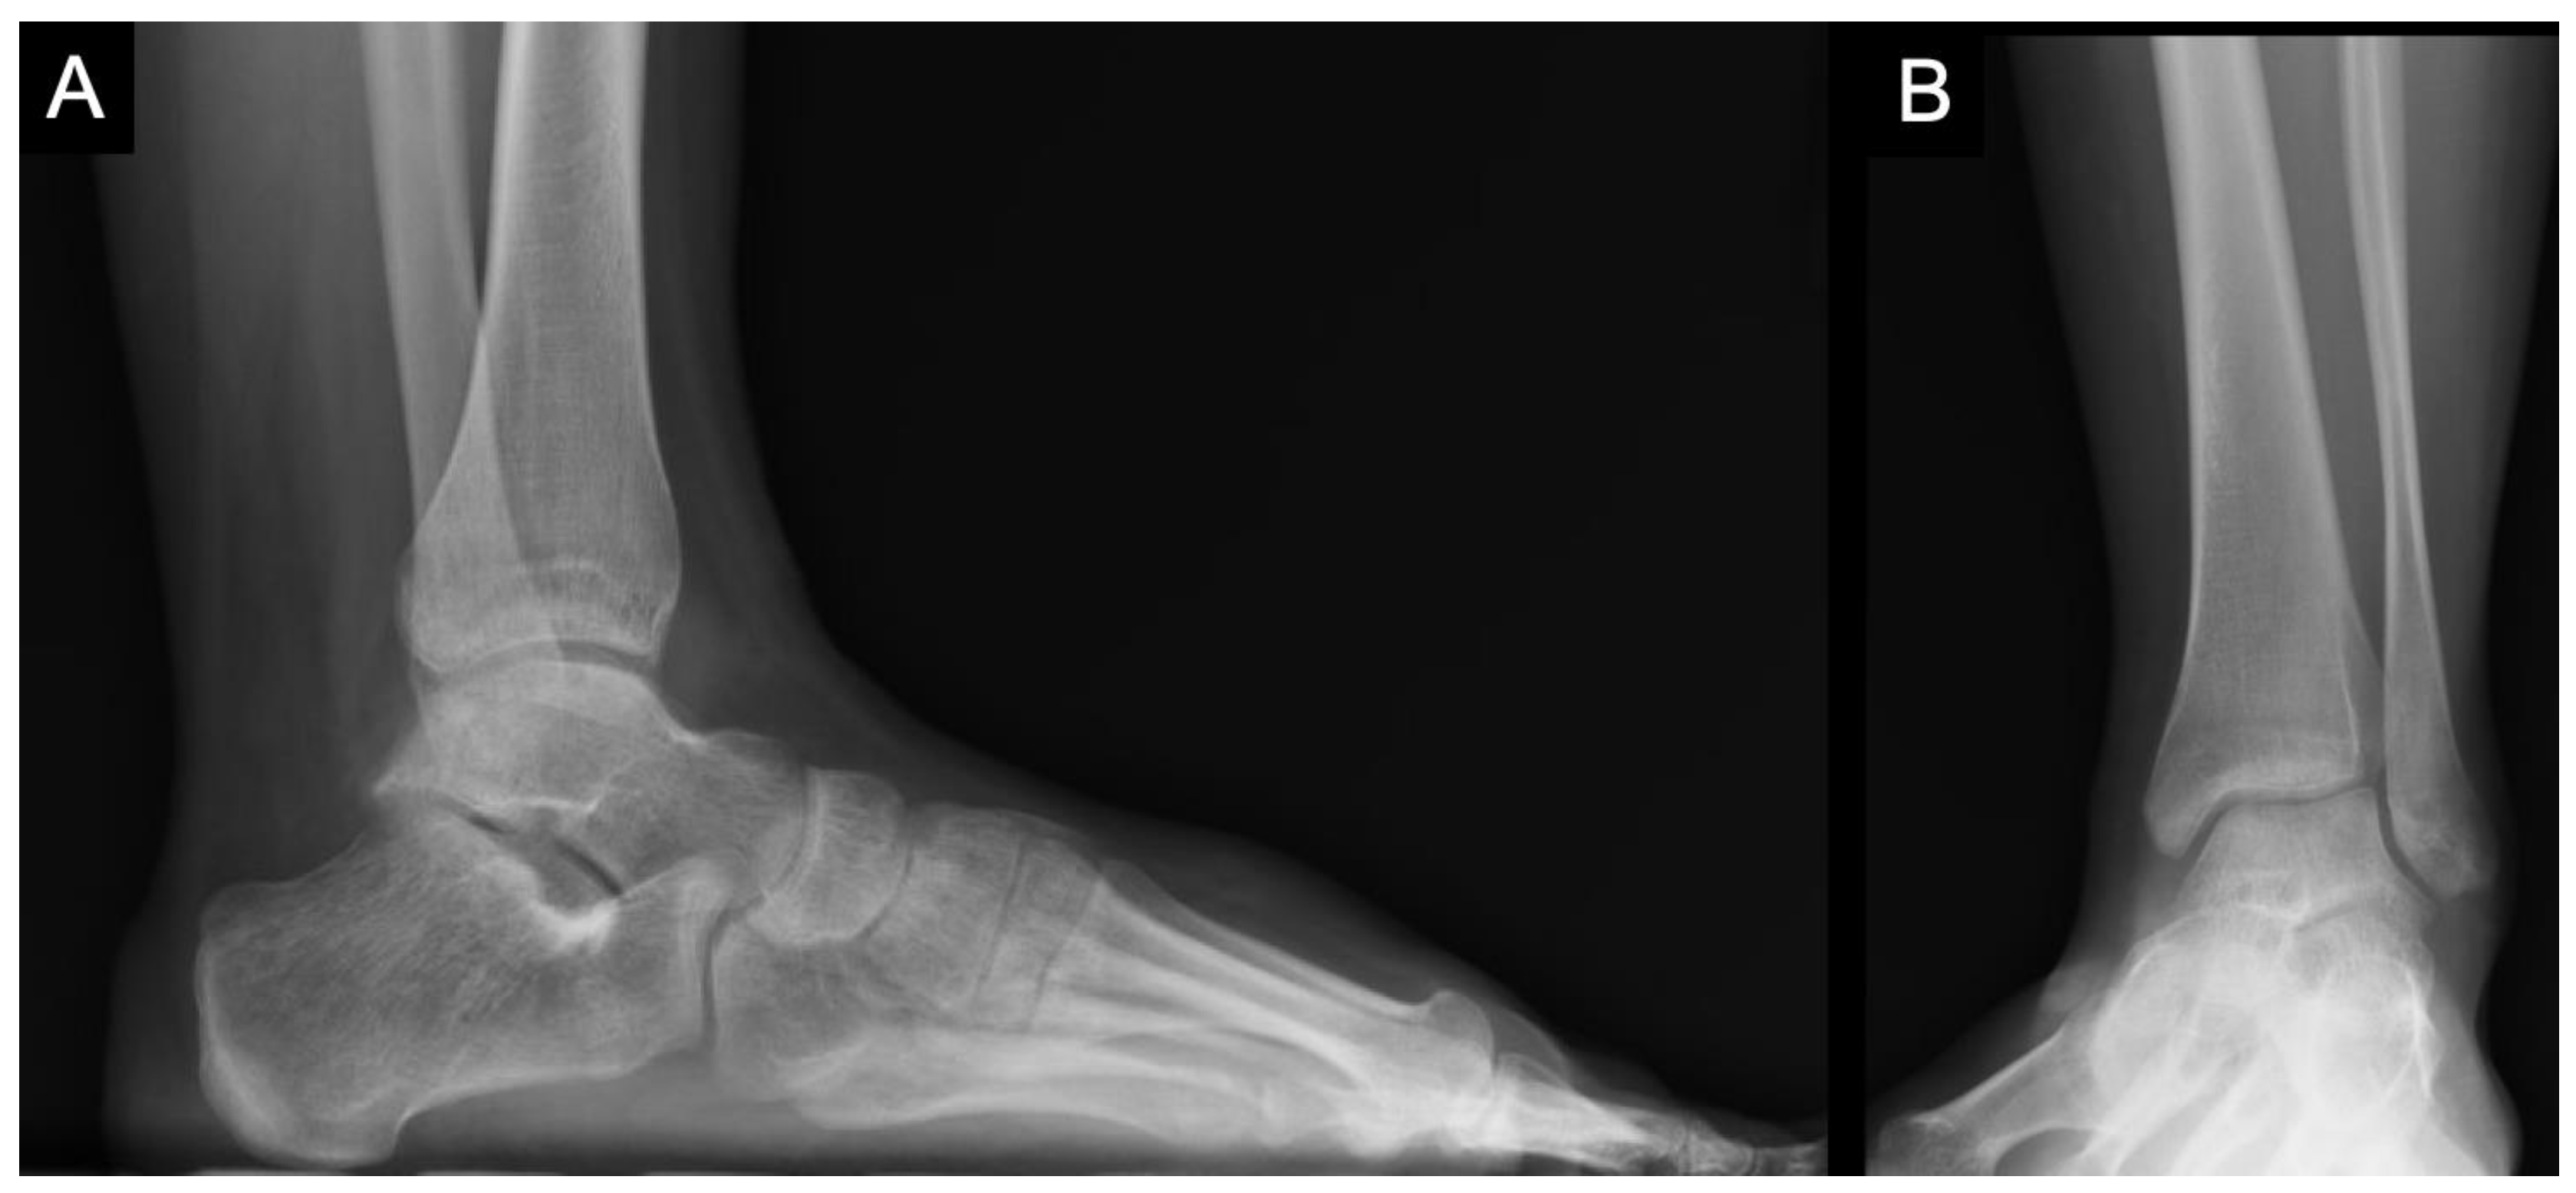

From www.researchgate.net

Talar avascular necrosis (AVN) preand postoperative imaging. (A, B)... Download Scientific Talar Bone X Ray Osteochondral lesions of the talus are focal injuries to the talar dome with variable involvement of the subchondral bone and cartilage which may. The os trigonum is a normal variant of talar anatomy, representing an unfused lateral. Tali 4), historically known as the astragalus, is a tarsal bone in the hindfoot that articulates with the tibia, fibula,. Diagnosing talus bone. Talar Bone X Ray.